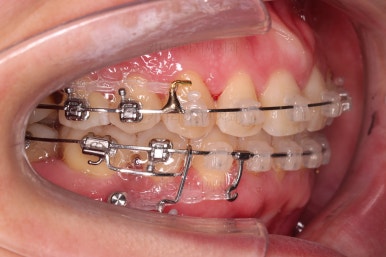

중앙선 개선을 위해 미니스크류와 다양한 장치를 활용해 주고요.

발치 공간도 많이 줄었네요.

중앙선, 교합 등을 더 신경쓰고 마무리를 합니다.

마무리 전에 부산교정치과 충치치료도 깔끔히 진행하게 됩니다.

위아래 좌우 치아가 없는 위치가 모두 달랐지만 교합도 잘 구성했고요.

아무래도 좌우 치아 크기들이 다르다 보니(뽑은 치아가 다르니) 중앙선은 100% 일직선은 안맞더라도 매우 정상 범주로 마무리를 할 수 있었습니다.

특히 어금니에 보이던 충치도 깔끔하게 마무리 했고요.